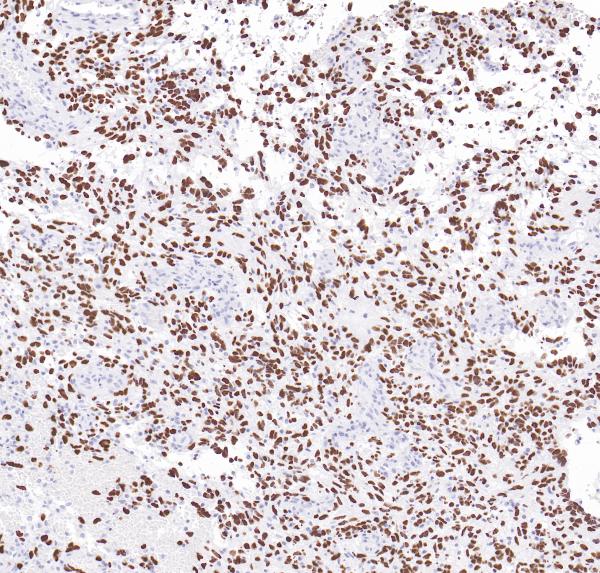

H3K27M

BP6294